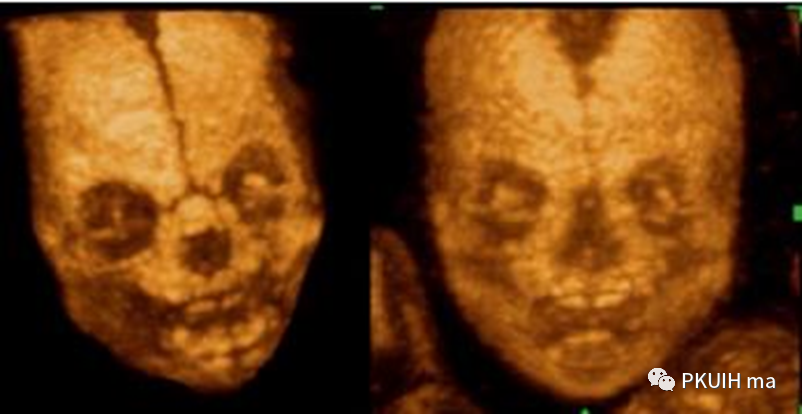

骨骼模式显示缺如的鼻骨(右侧图鼻骨缺如,左侧正常)

三维显示胎儿面横裂

早孕三维